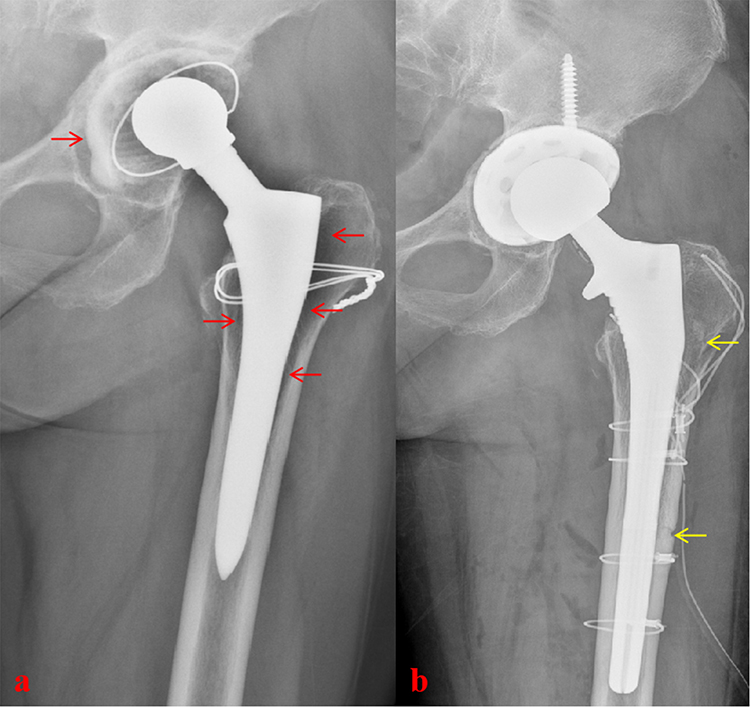

Understanding Hip Implant Components in Revision Surgery

A total hip replacement consists of several components that may fail over time. In revision hip replacement surgery in Surat, Dr. Krunal Donda evaluates which components require replacement: the acetabular cup (socket), femoral stem, femoral head (ball), and polyethylene liner.

Understanding component failure is crucial for successful revision hip surgery. Some revisions involve only the acetabular side, others only the femoral side, while complex cases require complete revision of all components with extensive bone reconstruction. Dr. Donda's expertise in complex hip revision surgery ensures optimal component selection and surgical technique for each patient at Shivaan Hospital.